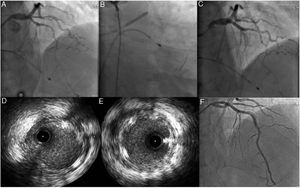

A e B: Coronariografia evidenciando artéria coronária direita (CD) com disseção espontânea desde o segmento médio com trombo condicionando fluxo TIMI 1. C: Imagem de IVUS mostrando disseção desde o ramo póstero‐lateral até ao segmento médio da CD com grande quantidade de trombo. D: Implantação de três stents com fármaco em overlap. E e F: Imagem de IVUS mostrando stents com boa expansão e aposição e protrusão de trombo (seta).

Dado o doente se encontrar ainda com dor durante a coronariografia diagnóstica, foi decidido proceder a angioplastia da coronária direita com apoio de imagem intravascular, com implantação de três stents diretos Resolute Onyx ® 3,5mm/30mm no segmento distal, 4/38mm proximal a este e com overlap e 4mm/22mm proximal a este último e com overlap, ficando com fluxo final TIMI 2 na descendente posterior e póstero‐lateral. Na imagem de controlo pós‐angioplastia com IVUS verificou‐se uma boa aposição e expansão dos stents, a presença de hematoma intramural, alguma protrusão de trombo intrastent e ainda de algum trombo na póstero‐lateral (Figura 1).